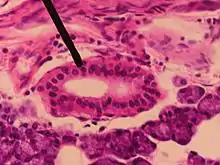

Striated duct

Striated duct in Parotid gland

A striated duct (Pflüger's ducts ) is a gland duct which connects an intercalated duct to an interlobular duct. It is characterized by the basal infoldings of its plasma membrane, characteristic of ion-pumping activity by the numerous mitochondria.[8][9] Along with the intercalated ducts, they function to modify salivary fluid by secreting HCO3 and K+ and reabsorbing Na+ and Cl using the Na-K pump and the Cl-HCO3 pump, making the saliva hypotonic.

Their epithelium can be simple cuboidal or simple columnar.[10]

Striated ducts are part of the intralobular ducts.

They are found in the submandibular gland,[11][12] sublingual duct, and the parotid gland, but are more developed in the parotid gland.[13]

They are not present in pancreas.